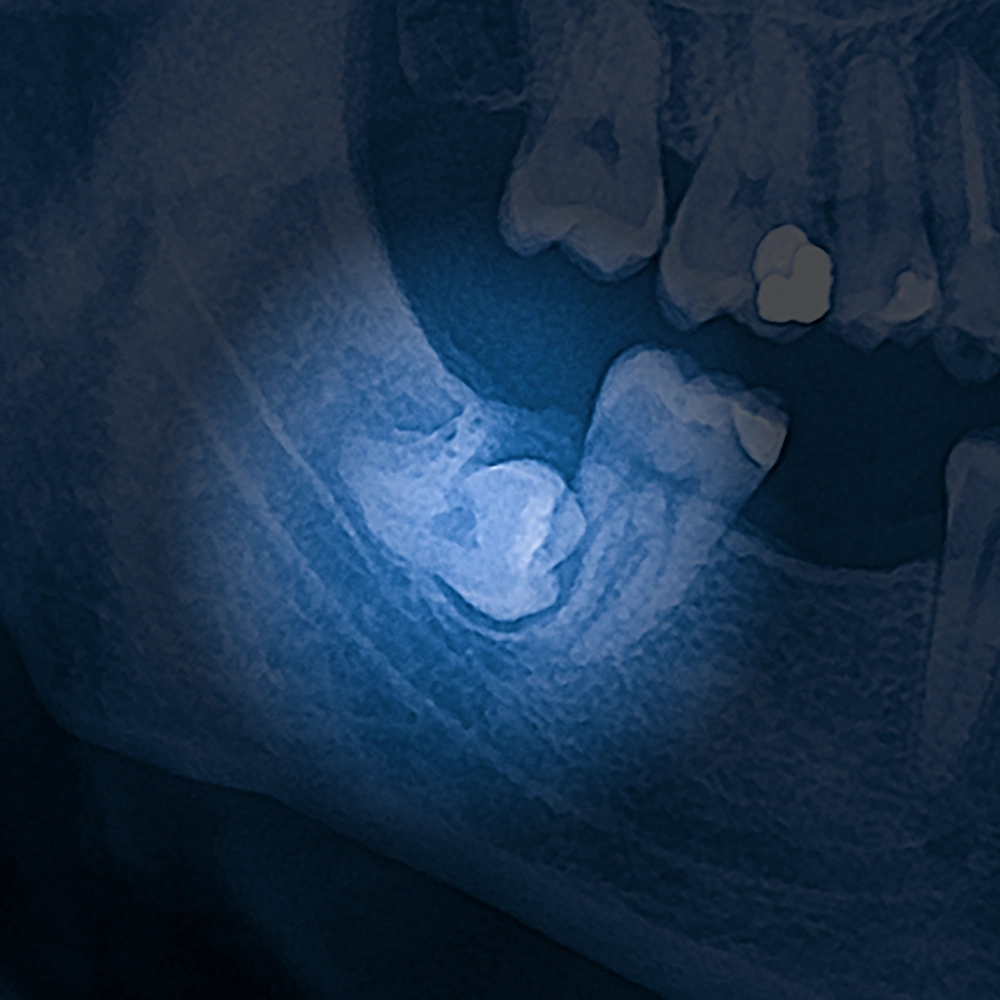

X-rays of an impacted wisdom tooth.

The Extraction Procedure

On the day of the extraction, we make sure patients feel fully prepared and at ease. Using the latest techniques, Dr. Harriman carefully removes wisdom teeth with minimal impact on surrounding tissue. The procedure is typically quick, and we work hard to keep any discomfort to a minimum, both during and after the surgery.